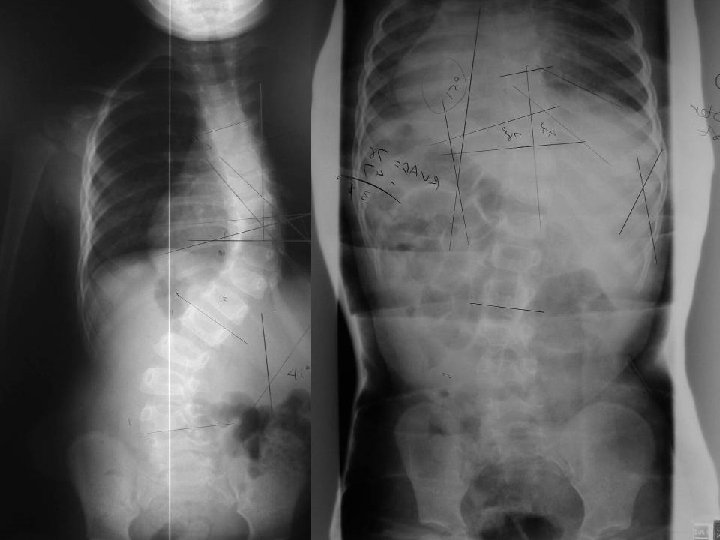

Pre and Post Casting Age 2 years Age 7 mo